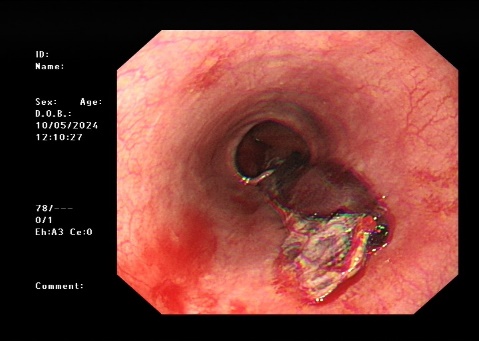

5.新疆医院多学科通力合作,成功救治一名危重症患者

5月9日,在重症医学科副主任驻疆专家王春亚、消化内科驻疆专家史海涛、心血管内科驻疆专家韩捷、麻醉科驻疆专家袁浩峥的全力协作下,成功救治一名反复呕血伴肾衰和高血压的危重症患者,体现新疆医院多学科联合救治能力。

治疗前胃镜检查结果

治疗后胃镜检查结果